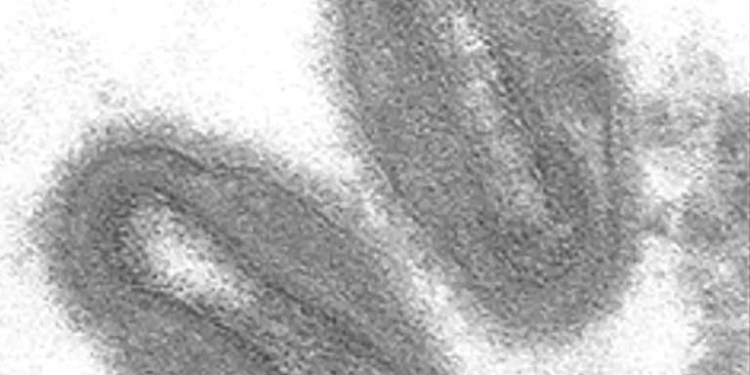

La Dirección Nacional de Epidemiología confirmó este jueves cuatro nuevos casos de viruela símica en el departamento de Santa Cruz, con lo cual sube a diez los pacientes infectados con la enfermedad en Bolivia.

Según la autoridad de Salud, la cepa que circula en el país, es benigna y tiene un grado de letalidad del 1%, la misma que está presente en el continente americano.